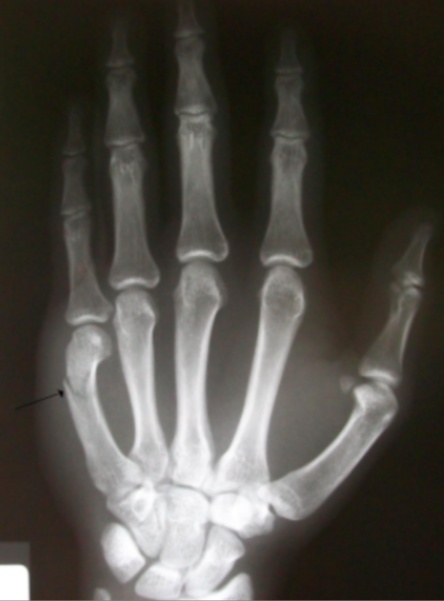

Boxer

The most common metacarpal fracture, involving the distal 5th metacarpal (specifically the neck).

A boxer fracture is typically the result of the patient punching a hard object.

A boxer fracture will present with marked swelling around the 5th metacarpal and possible rotational deformity.

Nondisplaced boxer fractures are treated with an ulnar gutter splint, displaced and unstable fractures are treated with surgical pinning or open reduction internal fixation.

Boxer fractures that are actual fight wounds may involve skin penetration by another persons mouth and are considered open until proven otherwise. This “fight-bite” often requires antibiotic treatment as the wound has been exposed to oral flora.